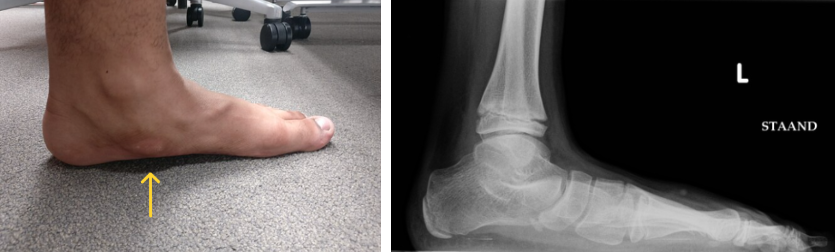

평발(편평족)과 밀접한 연관이 있는데, 평발이 있으면 발 아치가 무너지면서 부주상골에 가해지는 힘이 커져 통증이 발생하기 쉽습니다.

특히 후경골건이 부주상골에 부착되어 이 힘줄의 기능 불안정이 발 아치 붕괴와 통증을 유발할 수 있습니다.

평발로 인한 아치 붕괴와 보행 패턴 이상

병력 청취와 신체 검진을 통해 발 안쪽 돌출된 부위와 압통, 부종을 확인합니다.

엑스레이 검사로 부주상골의 존재 유무와 크기를 확인하며, 평발 여부도 평가합니다.